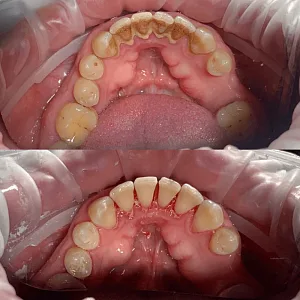

До и после

Результаты лечения